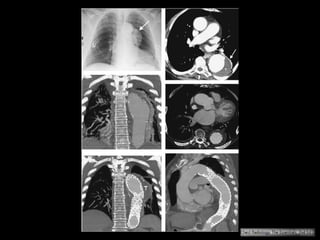

Dissecção aórtica

Achados de imagem:

RX tórax:

• Valor limitado: em 50% dos casos está normal;

• Alargamento do mediastino;

• Sinal da calcificação deslocada;

Angiotomografia

• Método de escolha;

• Protocolo:

Fase sem contraste: da croça até a bifurcação: útil

para diagnóstico de hematoma intramural e de

derrames hemorrágicos;

Colimação de 2,5mm.

• Fase com contraste:

Colimação fina: 0,625 a 1,5 mm;

Estuda-se do opérculo torácico até a sínfise púbica;

Delay: usar bolus timing;

Tratamento:

Stanford A: cirúrgico

O acometimento da aorta ascendente ocorre em

50-75% das dissecções;

Complicações fatais relacionados à extensão da

dissecção às coronárias, valva aórtica, pericárdio ou

pleura;

Artefatos de movimento na raiz da aorta;

Fase adicional curta com gating cardíaco.